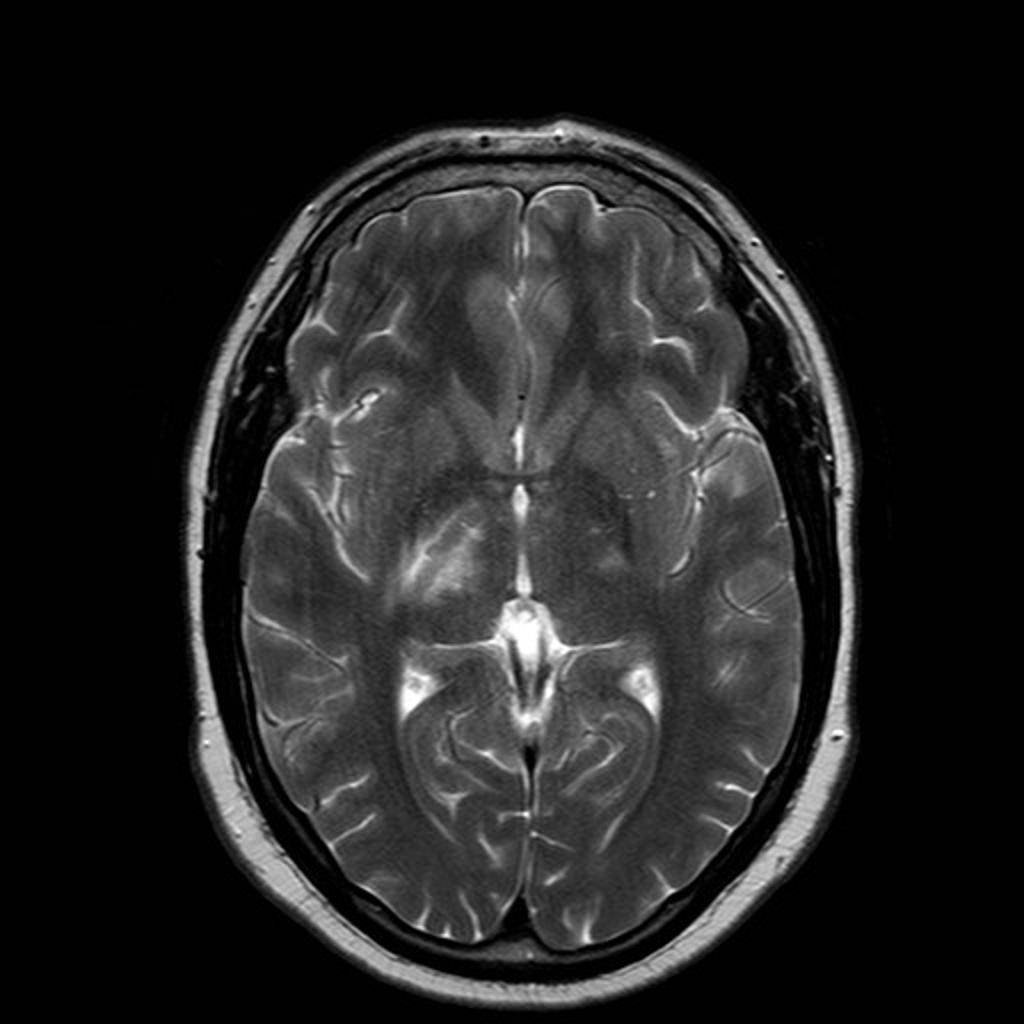

Publié 7 juin 2015 à 1024 × 1024 dans Sclérose en plaque et pathologies démyélinisantes

Case courtesy of Dr Yune Kwong, Radiopaedia.org. From the case Neuro-Behcet’s disease